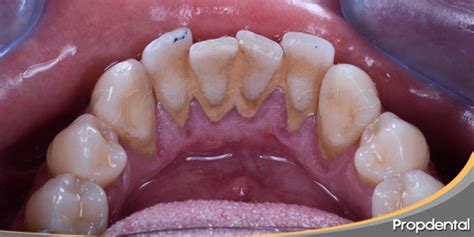

La prevención es clave para evitar la acumulación de sarro dental.

Los tratamientos de limpieza profesional en la clínica eliminan una mayor cantidad de sarro.